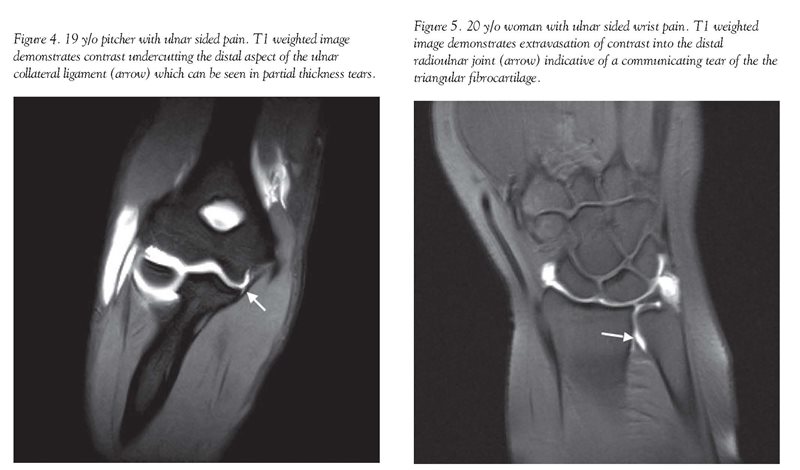

For the elbow, MR arthrography can aid in evaluating osteochondral lesions, joint bodies, and ligament tears. In particular, MR arthrography aids in the evaluation of the ulnar collateral ligament in athletes with pitching-related injuries. With the increase in participation in high level sports programs, such as year-round baseball/softball, these injuries are becoming more commonplace. Intra-articular contrast is useful in evaluating the ligaments which provide stability during the valgus stress of overhand throwing, and is critical in the assessment of partial thickness tears [Fig. 4].[9]

In the wrist, traditional arthrography and now MR arthrography have been utilized to detect the extension of contrast through communicating tears of the triangular fibrocartilage and intrinsic wrist ligaments [Fig. 5]. Unlike traditional arthrography, MR arthrography also can accurately assess fractures and avascular necrosis, and can delineate tendinosis or tendon tears.[10][11][12]